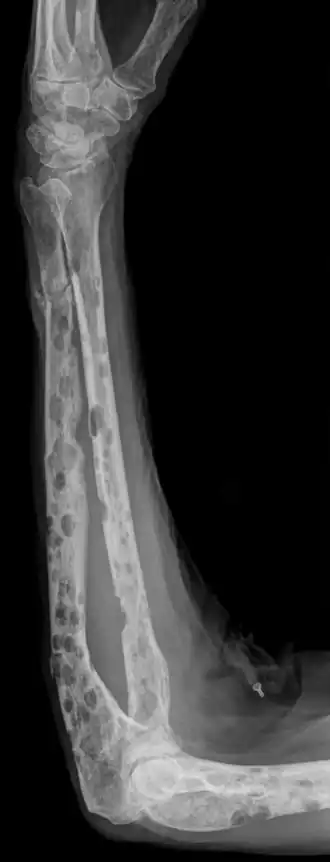

botafbraak in onderarm tgv Multipel myeloom

Als kwaadaardige plasmacellen het beenmerg innemen, kan de productie van rode bloedcellen, bloedplaatjes en witte bloedcellen in de vorm van neutrofielen in het gedrang komen. Hierdoor kunnen dan respectievelijk bloedarmoede, blauwe plekken en infecties optreden. De eerste symptomen zijn vaak echter botpijnen die ontstaan door zogenaamde osteolytische letsels. De kwaadaardige plasmacellen produceren namelijk OAF (Osteoclast Activating Factor), een eiwit dat aanzet tot botafbraak. Door deze botafbraak kan het calciumgehalte in het bloed verhoogd zijn (hypercalciëmie), wat aanleiding kan geven tot misselijkheid, verminderde eetlust, neurologische afwijkingen, hartklachten, jeukende ogen en obstipatie. Op termijn kunnen er ook nierbeschadigingen optreden ten gevolge van verhoogde eiwit- en calciumuitscheiding. De botten worden hierdoor broos en pijnlijk. Ook pathologische botbreuken en compressie van het ruggenmerg kan optreden bij deze patiënten. Bij de ziekte van Kahler worden veel defecte eiwitten (immunoglobulines) geproduceerd, die kunnen neerslaan in bijvoorbeeld de nieren. Nierfunctiestoornissen kunnen dan ook voorkomen bij de ziekte van Kahler. Indien er tevens amyloïd (onderdeel van de defecte eiwitten) afgezet wordt, kan men spreken van de ziekte amyloïdose.